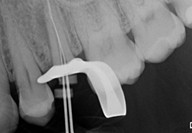

► Determinazione della lunghezza di lavoro

Galleria fotografica